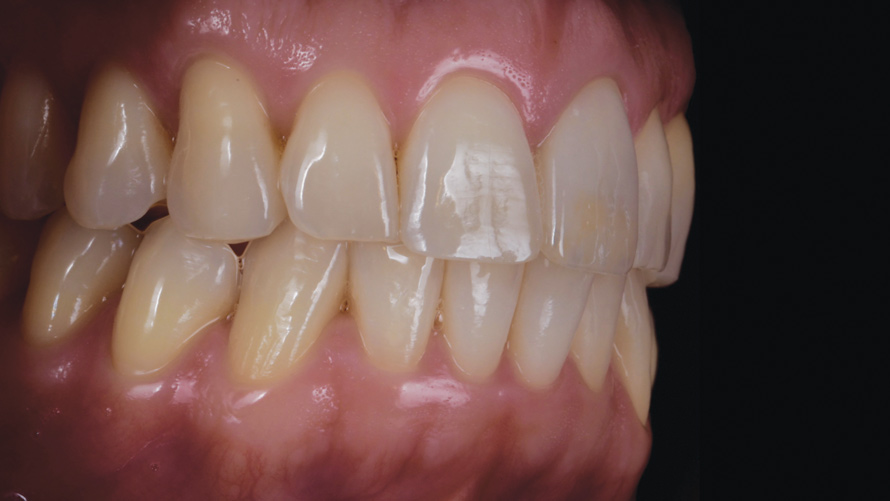

(17.) Case 2: Right- and left-side retracted profile views of the definitive all-ceramic restoration on the maxillary left central incisor.

Figure 17

Eight weeks after the initial start of the walking bleach procedure, the final layered lithium disilicate crown was tried-in and evaluated for function and esthetics. Upon patient approval, the intaglio surface of the crown was etched for 20 seconds with a 9.6% hydrofluoric acid etchant, rinsed, and then scrubbed with a 37.5% orthophosphoric acid solution to clean out any ceramic debris. The crown was then placed into an ultrasonic bath of 91% isopropyl alcohol for 5 minutes, after which the intaglio surface was coated with silane and placed under a warm air dryer for 1 minute. A translucent self-adhesive resin cement was used to bond the final restoration to the preparation. The patients both stated that they approved of the form, function, and esthetics of the definitive restoration and that they were very pleased with the final results (Figure 13 through Figure 18). Routine periodic evaluations and radiographs were scheduled to monitor their oral health and esthetics.